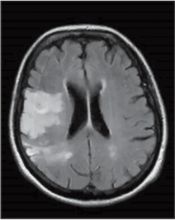

In diesem Leistungsbereich wird die Versorgung von Patienten mit der Hauptdiagnose cerebrale transitorische Ischämie, Intracerebrale Blutung, Hirninfarkt und Schlaganfall in der stationären Erstversorgung des Schlaganfalls dokumentiert.